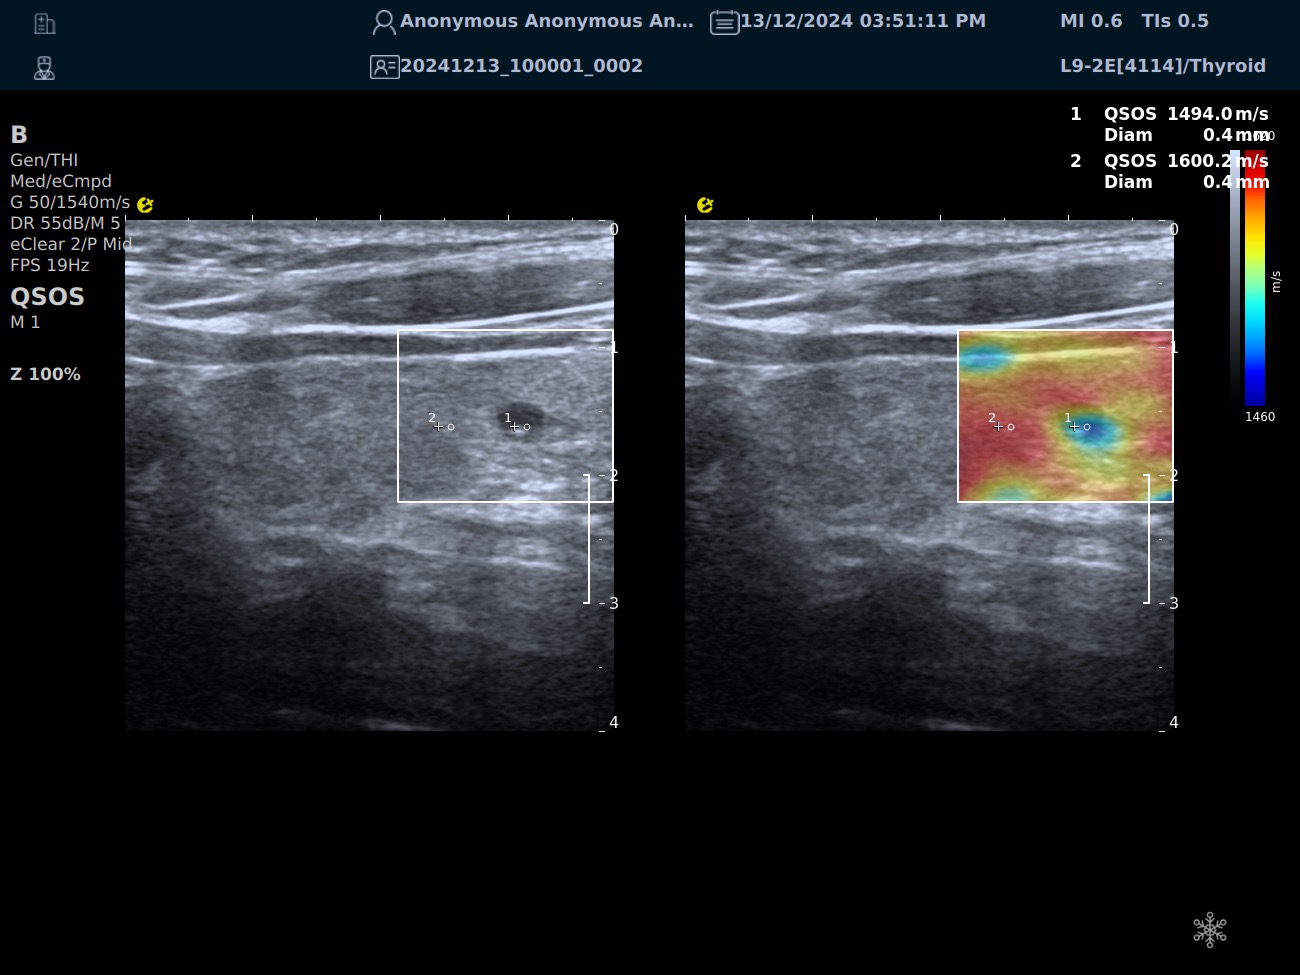

QSOS声速定量成像

QSOS声速成像技术利用声波在组织中的传播速度差异性,计算不同位置的声速值,反映组织的物理特性。

利用超声探头发射超声波脉冲,分析反射信号的时间延迟,确定声波传播路径和速度,构建声速分布图像。

QSOS技术采用彩色编码显示声速图像,不同颜色代表不同声速值,便于医生识别病变部位和测量。

技术优势

?精准定量反映组织特性,成像更敏锐?彩色编码直观显示,轻松发现异常?捕捉声速差异,早期、微小病变更易察觉

肌骨领域的应用

?精准定位损伤部位?判断损伤严重程度?监测肌肉营养?评估肌少症?骨质疏松评估